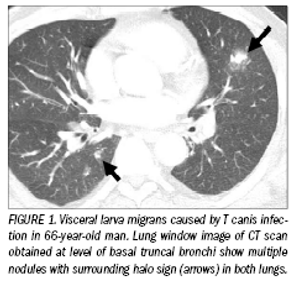

Imaging provides answersin parasitic infections

ByDae Wook Yeh, MD,Kyung Soo Lee, MD,Ho Yun Lee, MD

Parasitic infections are endemic in developing countries located in tropical and subtropical regions.